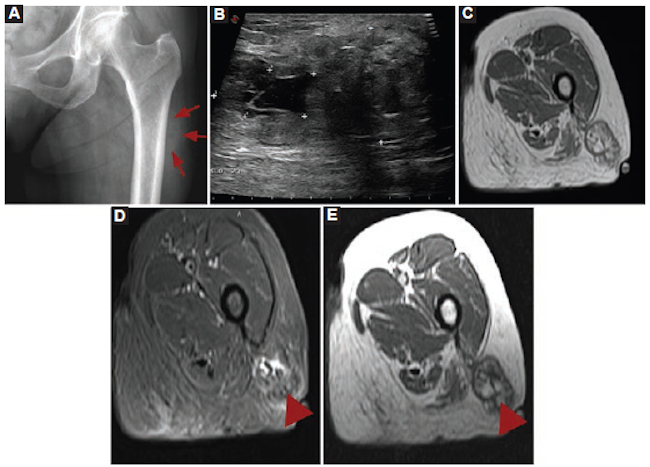

Mujer de 73 años con antecedentes de polimialgia reumática y arteritis de la temporal, que consultó por una masa en la región posterior del muslo izquierdo. En la exploración física no presentó signos de flogosis. Se solicitó ecografía, cuyo informe fue no concluyente. Posteriormente, se realizó una RM. Entre los diagnósticos diferenciales se planteó la posibilidad de un tumor adiposo. Por sus características, no se descartó una lesión agresiva, como el liposarcoma y sus variantes (Fig. 8).

Se realizó punción-biopsia, con diagnóstico definitivo de esteatonecrosis, sin evidencia de neoplasia.